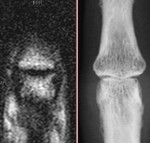

[画像診断]変形性関節症について【研修医と学ぶ】 2011-04-15